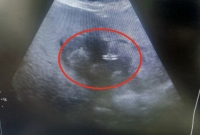

Учитывая преклонный возраст пациентки и сопутствующие риски, традиционное полостное оперативное вмешательство было сопряжено с высокой опасностью. Было выполнено малоинвазивное дренирование абсцесса печени под контролем ультразвуковой навигации. Эта методика позволяет с ювелирной точностью ввести дренаж в полость гнойника, минимизируя травматизацию тканей и ускоряя восстановление.

"Абсцесс печени без своевременной хирургической помощи может привести к сепсису и летальному исходу. Малоинвазивное дренирование под УЗ-контролем — это современный "золотой стандарт", позволяющий избежать высоких рисков кровопотери, инфекций и длительной реабилитации, характерных для открытых операций, особенно у пациентов старшего возраста", - говорится в сообщении.